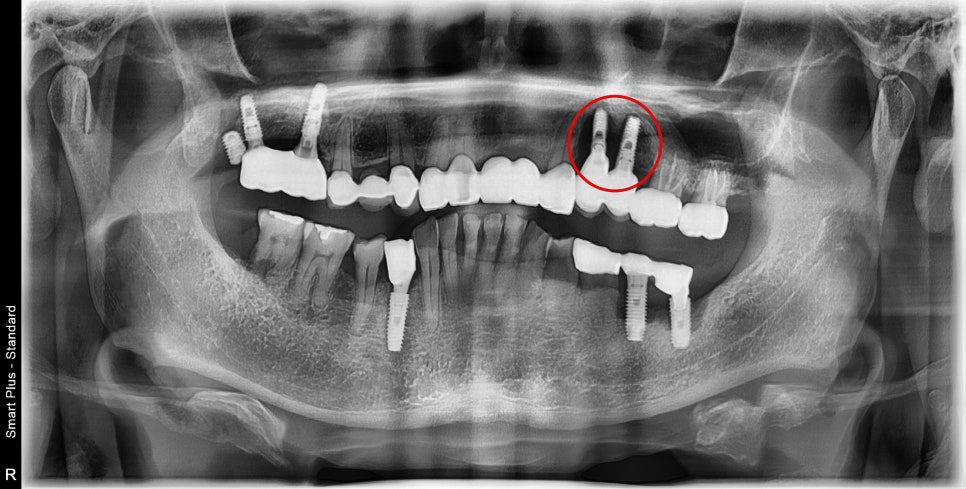

엑스레이에서 뭔가 뿌리 부분의 병변이 보입니다.

엑스레이상 임플란트 주변에 하얗게 보이는

치조골이라는 뼈가 보이지 않고

주변이 새까맣게 보이는 것을 보면 주변 뼈가

임플란트 주위염으로 인해 모두 소실된 것을 볼 수 있습니다.